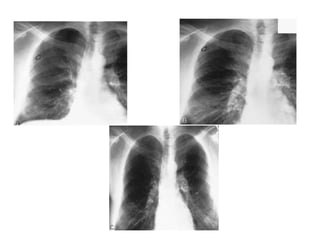

RADIOGRAPHICDIAGNOSIS

1- CXR

The standard procedure in making the diagnosis.

 It should be upright and preferably in the posteroanterior

projection. It is possible to miss a pneumothorax in a

semisupine portable anteroposterior view. If the patient

cannot be upright, a lateral decubitus view with the suspect

side positioned up may be helpful.

 A giant bulla can mimic a pneumothorax. Subtle lines demarcate

a bulla, which tends to be surrounded by thickened visceral pleura.

In addition, a pleural line can frequently be seen with lung

markings visible beyond the suspected bulla (double wall sign)

• British Thoracic Society guidelines for the

management of spontaneous pneumothorax,

recommend defining pneumothoraces as:

I. small defined as small rim of air around the

lung

II. moderate as lung collapsed halfway towards

the heart border

III. complete as airless lung, separate from the

diaphragm.